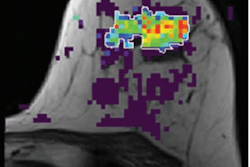

Which breast cancer patients should get preoperative MRI? The answer may not be as clear-cut as some would like to believe. A July 10 study in Radiology: Imaging Cancer found no patient- or tumor-specific factors predicted preoperative breast MRI outcomes.

The large, retrospective study included more than 1,000 breast cancer patients who underwent preoperative MRI to look for additional malignancies. While the study confirmed the benefits of preoperative MRI, the authors didn't find any characteristics linked to additional cancers.